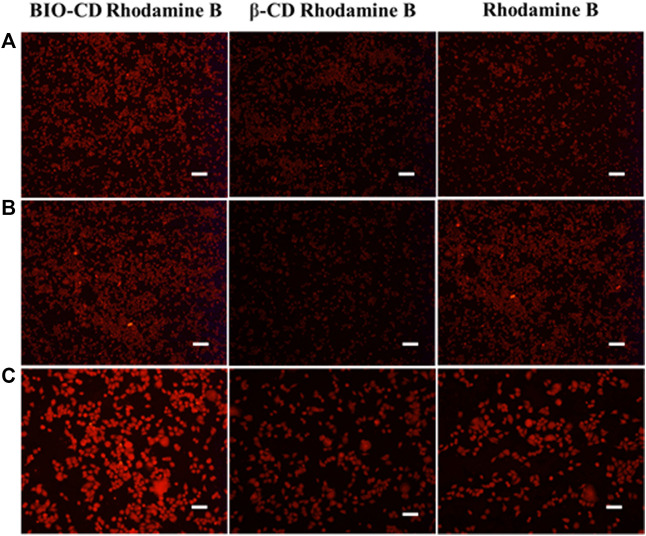

Selective Cellular Uptake

Through cell uptake studies on Hela, A549, and LO2 cells, the selective targeting properties of BIO-CD were determined. Cells were inoculated into culture dishes (20 mm, PS, 5,000 cells/dish), and then incubated overnight. The BIO-CD loaded with Rhodamine B was incubated with cells for 6 h. As Rhodamine B yields red fluorescence, it could be used to examine the intracellular localization of BIO-CD particles. The nucleus was identified by Hoechst staining, which yields blue fluorescence. Confocal laser scanning microscopy (CLSM, Eclipse Ti, Nikon) was used to record the intracellular localization of the samples. All cells were carried out in triplicate.

Cellular Uptake Assays

Rhodamine B (20 μg ml−1), Rhodamine B/BIO-CD inclusion complex (or Rhodamine B/β-CD inclusion complex) (20 equivalents) were co-cultured with LO2, HepG2 and Hela cells at 37°C for 2 h. Subsequently, cells washed three times with PBS, and cell uptake efficiency was observed with an inverted fluorescence microscope.

Therefore, the feasibility of targeted drug delivery of using BIO-CD was evaluated in our study. The model drug Rhodamine B was used to demonstrate that the BIO-CD polymer delivered the drug selectively to the biotin receptor overexpressed cancer cells. The two cell lines of HeLa cervical cancer and A549 human lung cancer have different biotin receptor expression levels on the cell membranes, thence, they are used as cell models. From the confocal image, the copolymer loaded with Rhodamine B was combined with HeLa cells selectively. But the fluorescence of the cell surface of A549 was negligible, indicating the biotin receptor targeting ability of BIO-CD (Figure 12).

Two model drugs Rhodamine B and Hoechst dyes were used to explain the selective drug delivery efficacy of BIO-CD. The microscopic images showed that Hoechst crossed the cell membrane, indicating that Hoechst entered the cytoplasm. We observed that massive Rhodamine B accumulated in the cell surface when incubated with HeLa cells for 4 h in the delivery experiment of Rhodamine B. This result was significantly higher than Rhodamine B without using BIO-CD (Figure 13). Consequently, it proved that the BIO-CD could bind to biotin receptors selectively, mediated the absorption and accumulation of Rhodamine B in cells. Due to the enhanced cellular intake of the polymer-drug complex, the inclusion complex of AD-CBD/BIO-CD has much higher cytotoxicity than free AD-CBD.

Cellular Uptake Assays

We studied the capability of BIO-CD to promote the uptake of guest molecules in tumor cells. Rhodamine B was used as a model drug. Hela, HepG2, and LO2 cells were incubated with the inclusion complex of BIO-CD or ß-CD in media for 1 h. Meanwhile, we had observed a similar situation with ß-CD in normal cells LO2. As shown in Figure 14, after Rhodamine B entered the cavity of BIO-CD, it could enhance the efficiency of cell fluorescence imaging, while ß-CD was opposite. This might attribute to that BIO-CD specifically binded to the over-expressed biotin receptor on the surface of tumor cells, which resulted in the enhanced drug uptake. Because ß-CD did not have the targeting ability of biotin, and LO2 cell surface did not have the over-expressed biotin receptor, these possibly reduced the uptake capacity of cells. Data mentioned above confirmed BIO-CD successfully encapsulated guest drug and specifically bound to the biotin receptor to enhance the cellular uptake.